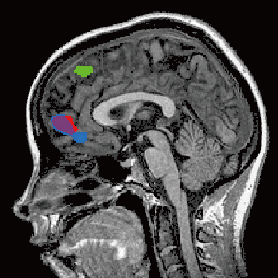

The authors found that humans simulate the decisions of other people using two brain signals encoded in the prefrontal cortex, an area responsible for higher cognition (Figure 1). One signal involves the estimated value of the reward to the other person, and is called the reward signal, referring to the difference between the other's values, simulated in one's mind, and the reward benefit that the other actually received. The other signal is called the action signal, relating to the other's expected action predicted by the simulation process in one's mind, and what the other person actually did, which may or may not be different. They found that the reward signal is processed in a part of the brain called the ventromedial prefrontal cortex. The action signal, on the other hand, was found in a separate brain area called the dorsomedial prefrontal cortex.

Figure 1: Neural activity for the simulation of another person: reward signal (red) and action signal (green).

The action signal shown in this figure (green) is in the dorsomedial prefrontal cortex. The activity of reward signal (red) largely overlaps with the activity of the signal for the self-valuation (blue) in the ventromedial prefrontal cortex.